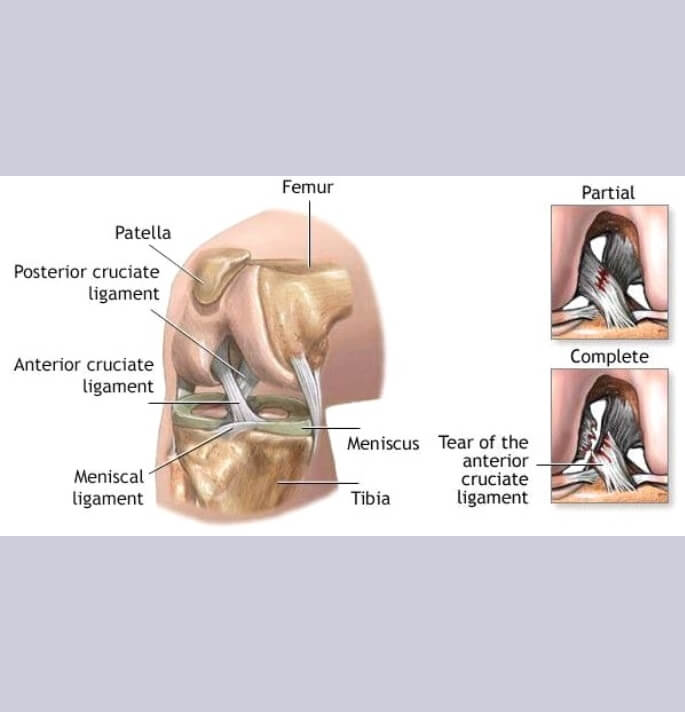

Kruisband letsels

Voorste kruisband letsels zijn meer voorkomend en meer invaliderend dan de achterste kruisband letsesl en ontstaan typisch bij een flexie, valgus, rotatietrauma met een gefixeerde voet.

Behandeling van deze letsels kan conservatief (niet operatief) met een specifiek oefenschema onder begeleiding van een kinesist

Operatieve behandelingen zijn aangewezen bij jongere patiënten welke sport actief wensen te blijven en welke duidelijke subjectieve instabiliteitsklachten ondervinden.

Bij een reconstructie (herstel) van de kruisband wordt een eigen peesgreffe (autologe) van de hamstrings (semitendinosus pees) of een strip van de quadricepspees gebruikt.

Deze peesgreffe wordt via een tunnel in het onderbeen (tibiale tunnel) in het gewricht gebracht (intra-articulair) en in een bovenbeen (femorale) tunnel gefixeerd.